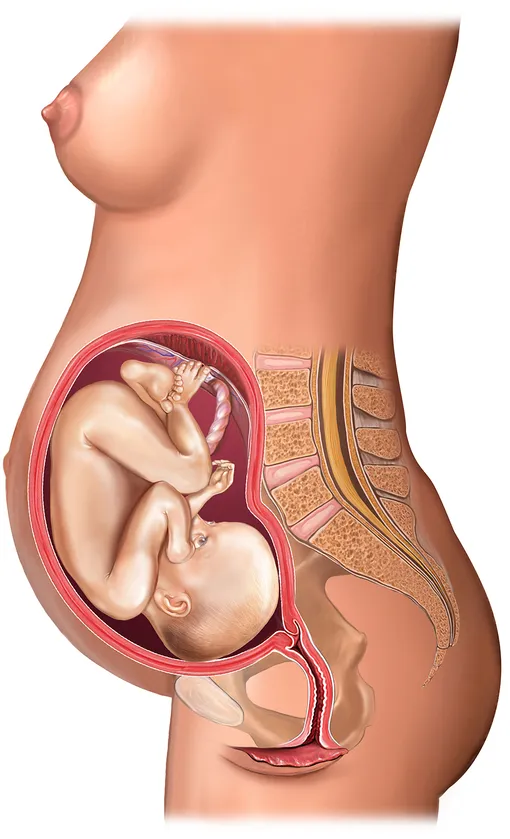

Расположение плода на 15-й неделе беременности: фотографии и иллюстрации